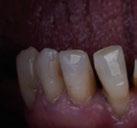

Exploración Intraoral

Presenta un estado oral deficitario. Parcialmente edéntula, con colapso de mordida, migración dental patológica, restauraciones de resina antiguas fisuradas y filtradas, transparencia y exposición de cámara pulpar secundaria a desgastes con pérdida de estructura e integridad de tejido dental importante (Figuras 1 a 4). Portadora a tiempo parcial de prótesis removibles desadaptadas de más de 10 años de antigüedad, refiriendo incapacidad de adaptación a este tipo de prótesis.

Figura 3. Visión intraoral oclusal mandibular. Figura 4. Visión intraoral frontal. Figura 1. Visión intraoral oclusal maxilar. Figura 2. Visión lateral izquierda intraoral. Figura 7. Escaneado intraoral maxilar con Dexis IS3700. Figura 8. Escaneado intraoral mandibular con Dexis IS3700. Figura 5. Visión extraoral lateral sonrisa.